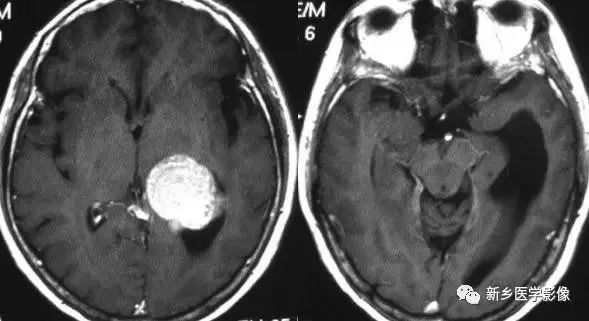

❹ 一侧室间孔阻塞

脑脊液主要产生于脑室的脉络膜丛。当一侧室间孔阻塞时,同侧侧脑室脉络膜丛产生的脑脊液不能进入三脑室,脑脊液在侧脑室内聚积,CT和MR检查表现为一侧侧脑室扩大,扩大明显时可有中线结构向对侧移位,主要原因有室间孔附近的肿瘤、囊肿、囊虫及炎性粘连。

确定一侧侧脑室扩大为室间孔阻塞所致的要点包括:

- 一侧侧脑室扩张明显,有张力;

- 透明隔向对侧移位;

- 扩一大的侧脑室周围没有能够导致该侧侧脑室扩大的其他可以解释的原因。